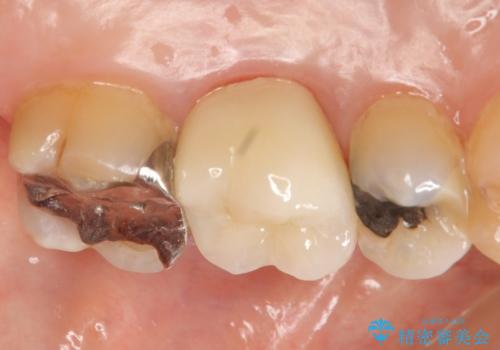

- 左上の奥歯にできものが出来てから口臭が気になるようになったので診て欲しいといらっしゃった方の症例です。

左上のできものは左上6の根尖病変が原因のフィステル(膿の出口)であったため、再根管治療を行いました。

フィステルの消失を確認後、オールセラミッククラウンによる補綴を行いました。